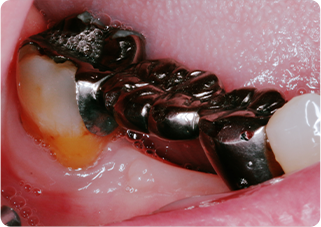

精密根管治療③

術前

術後

| 主訴 | 奥歯で噛むと痛い |

|---|---|

| 治療期間/回数 | 1ヵ月、4回 |

| 価格(税込) | 88,000円(税込) |

| リスク・副作用 | 病変再発、歯根破折の可能性 |

| ポイント | う蝕検知液を用い、むし歯の取り残しが無いようにし、ラバーダム防湿を行い、無菌的に根管治療を行った。根管充填材は、殺菌作用の強い保険適応外のMTAセメントを使用した。 |